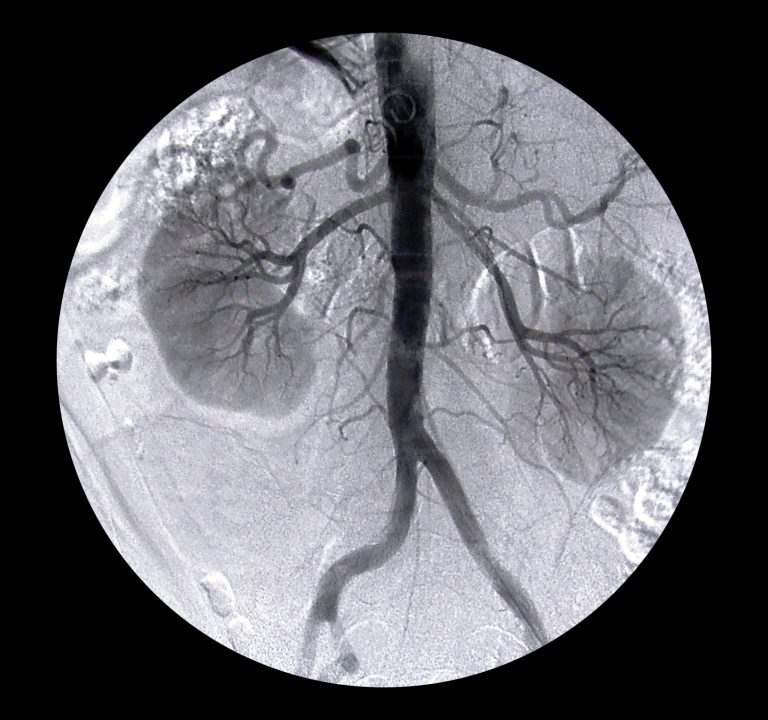

¿Sabias que cuando duermes tus riñones tienen la capacidad de regenerarse?(1)

¿A través de que mecanismos puede la melatonina promover la regeneración del riñón?

- Disminuye la hipertensión(2,3,4)

- Suprime mediadores inflamatorios y protege de la lesion inflamatoria y reduce el estrés oxidativo(5)

- Regula el ciclo circadiano del sueño-vigilia(6)

- Mejora la calidad del sueño (reparador)(7)

- Relajación del Sistema RAS (Renina-Angiotensina-Aldosterona)(8)

- Mejora el aporte de oxigeno nocturno al riñón (9)

- Disminuye la retención de sodio por la noche (10)

- Activación de la regeneración a partir de celulas madre renales (11)